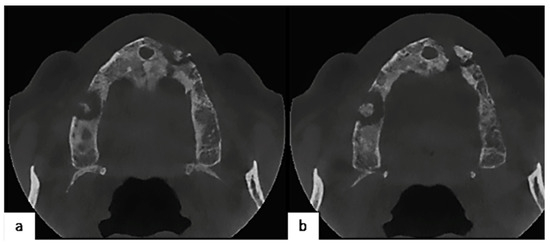

2.3. Clinical Findings and Diagnostic Assessment

2.4. Therapeutic Intervention

2.5. Follow-Up